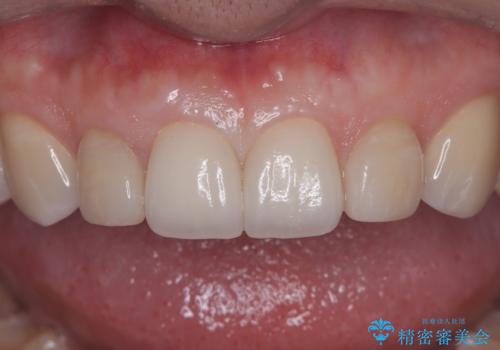

【セラミッククラウン】他院で治療したセラミッククラウンをやりかえたい

- 他院で1年ほど前にセラミッククラウンを入れたそうですが、しばらくしてから歯茎から膿が出てきたそうです。

歯髄診にて歯髄が失活していることが判明したため、クラウンを除去し根管治療を行ってから、再度オールセラミッククラウンを作成しています。

今回のケースはクラウン除去した際に露髄点は認められなかったため、形成時の発熱が原因であったと推測しています。